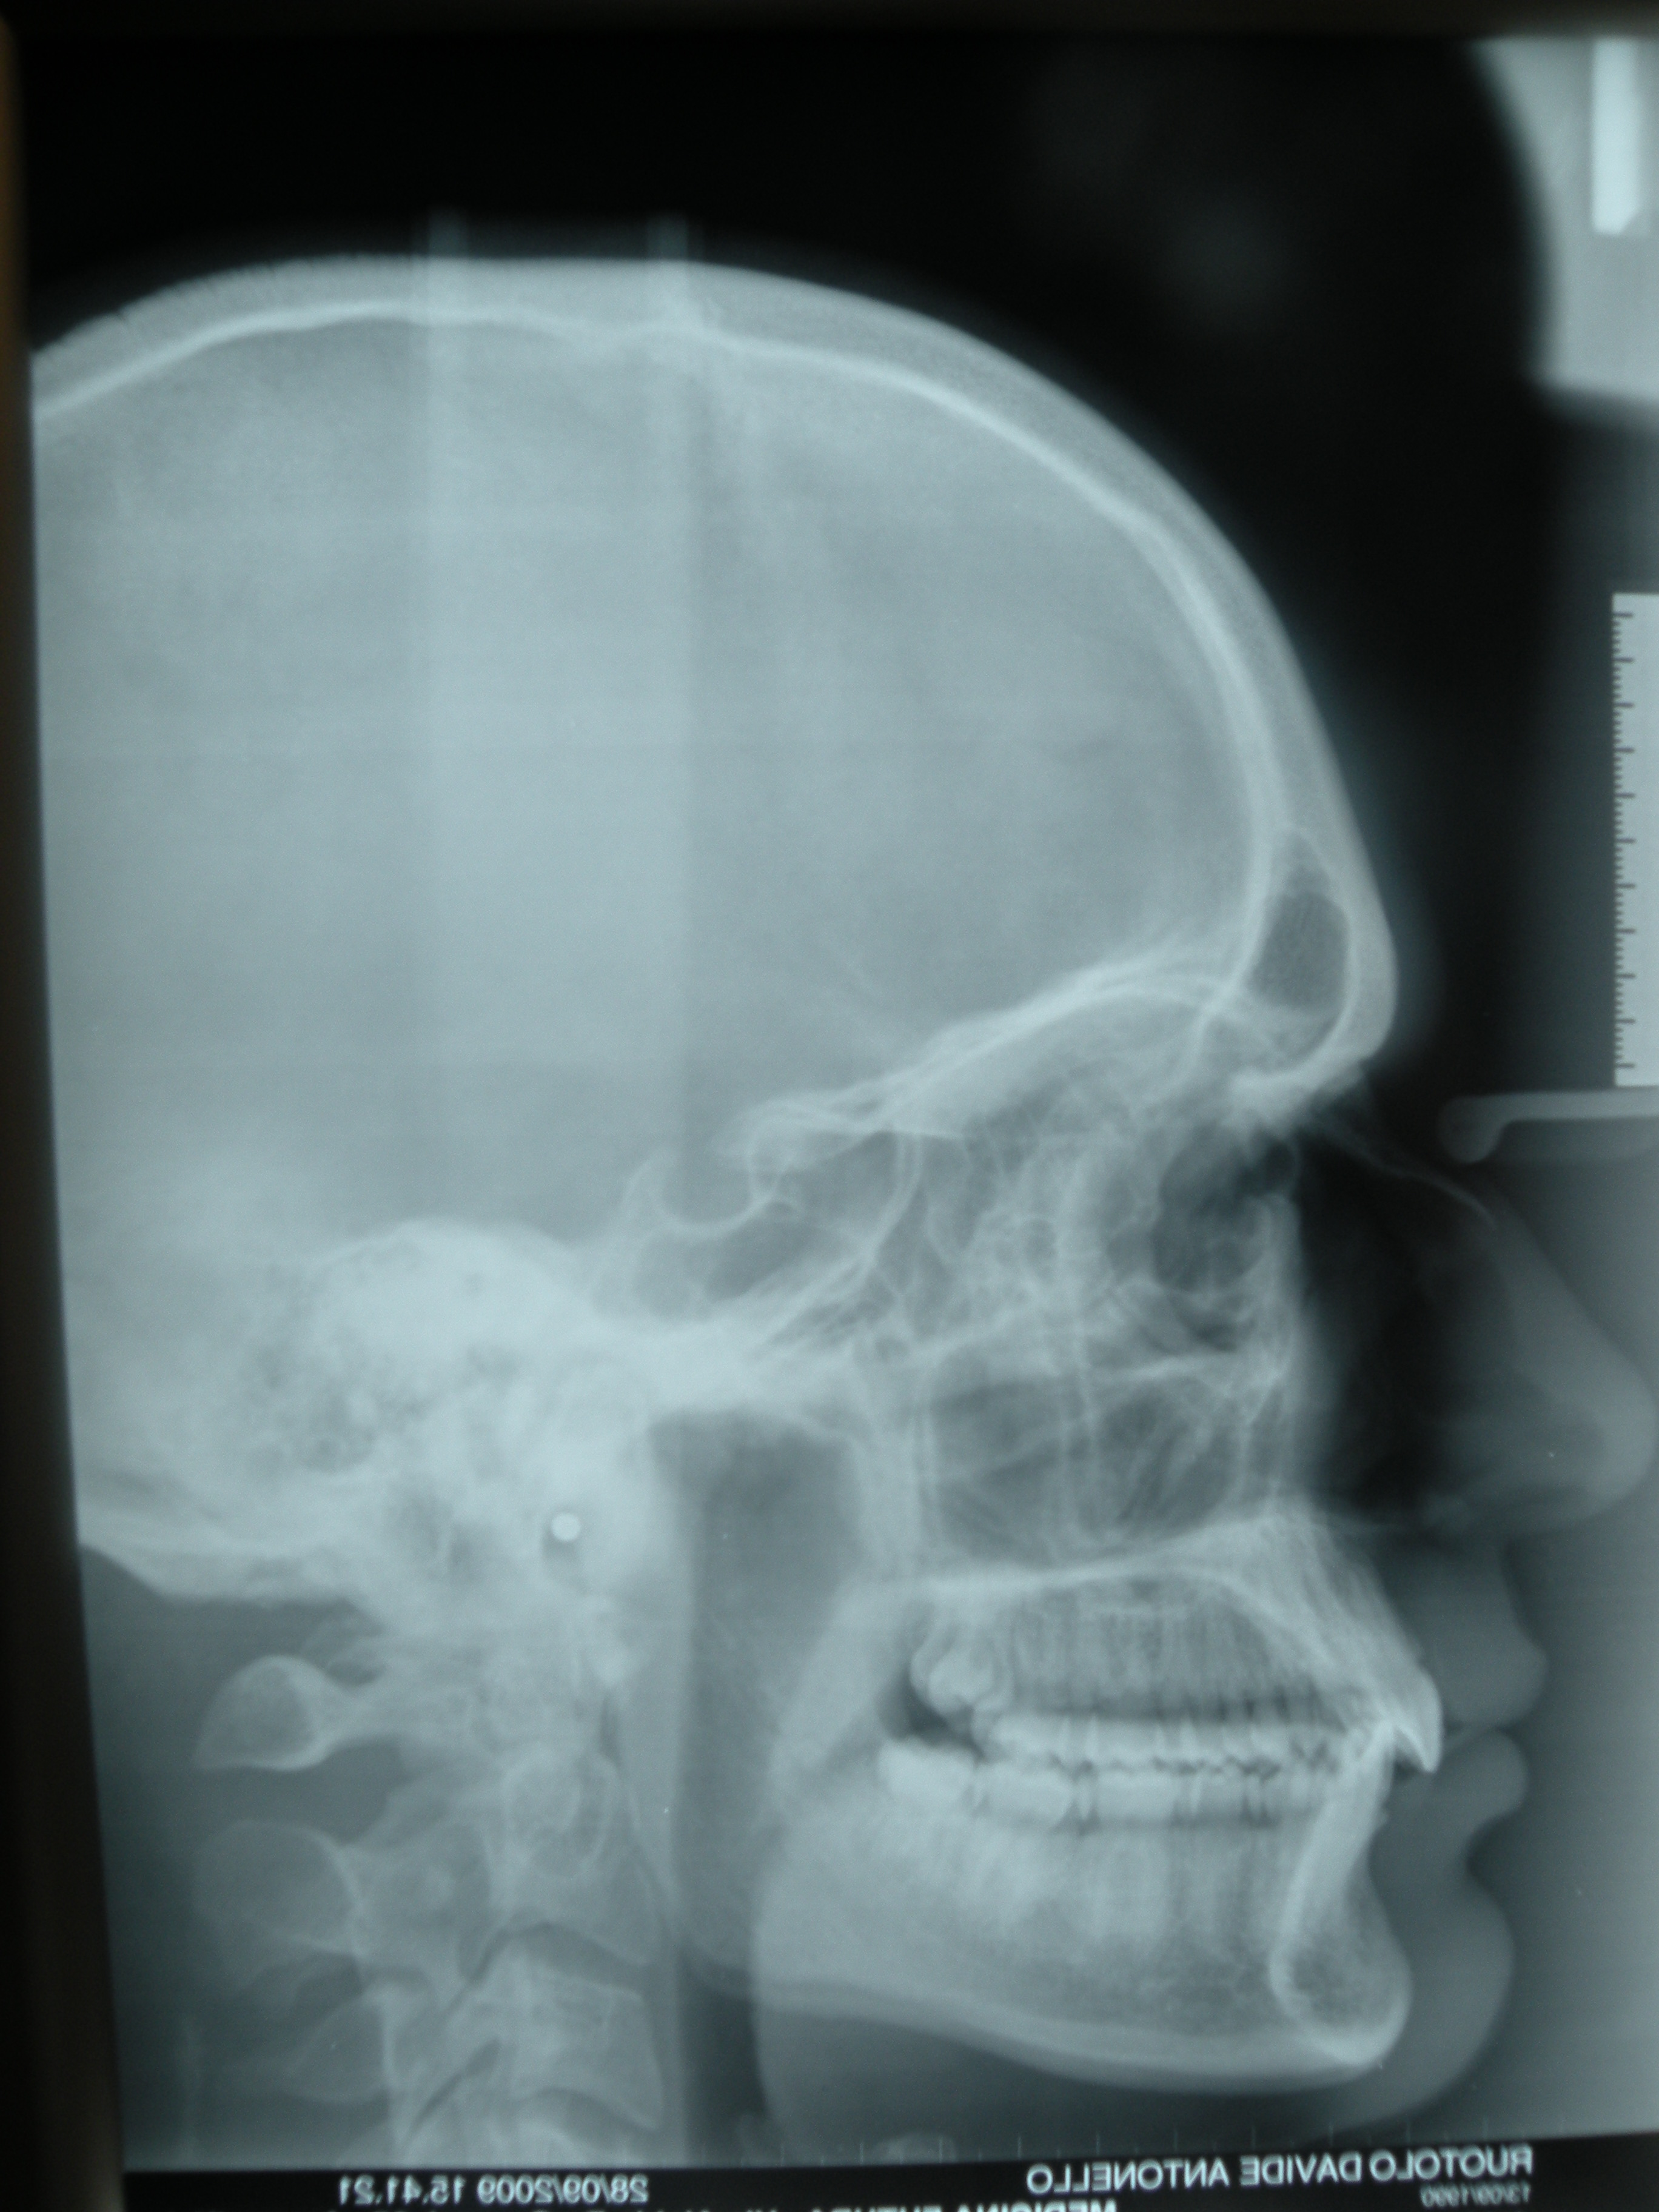

Paziente maschio, R. D., 22 anni, trattato con allineatori trasparenti Invisalign in 13 mesi.

telecranio